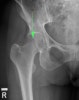

1. X-ray : Hip AP, Lateral view

X-ray : 대퇴골두 골절(Femoral head fracture)

2. CT scan : 골절편의 위치와 크기를 평가하고 동반된 비구 골절을 확인